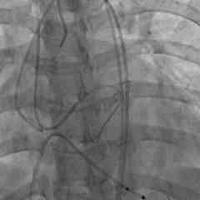

82岁老年女性,胸12椎体骨折。行球囊扩

82岁老年女性,胸12椎体骨折。行球囊扩张椎体成型术...

由 medjpg 发表于 2026-03-24 22:32